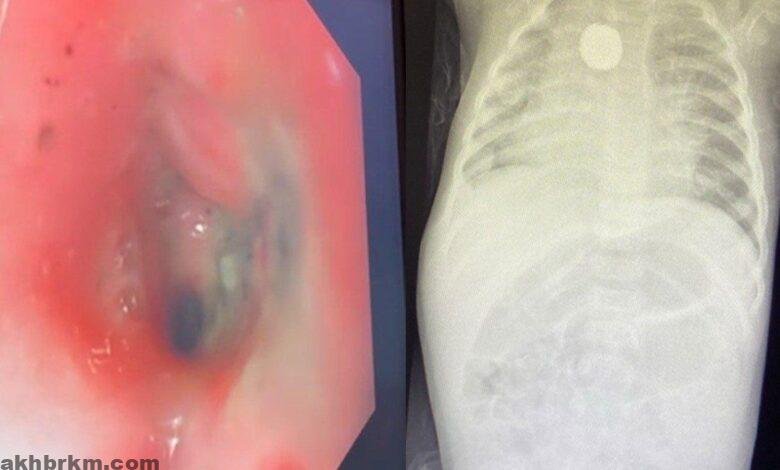

وعلى الفور أجريت الفحوصات اللازمة حيث جرى اكتشاف جسم غريب مما استدعى التدخل الطبي العاجل لإنقاذ الطفلة، وتم تكوين ثلاث فرق طبية لاستخراج البطارية الحارقة دون حدوث مضاعفات، متمثلة في فريق قسم المناظير، وجراحة القلب والشرايين، وجراحة الأطفال، وتبين من خلال الأشعة المقطعية وجود الجسم الغريب على مقربة من شرايين القلب، مختفياً في جدار المريء مع الضغط على الحنجرة المجاورة.

وأضاف تبين وجود حروق داخل المريء مع تضيق المنطقة المتأثرة وعدم رؤية الجسم الغريب مبدئيا وبعد عدة محاولات اتضح وجوده ملتصقاً ومغطى بأغشية الجدار داخليا، مما أتاح إمكانية سحبه بالمنظار بسلام دون حدوث ثقب أو نزيف في المنطقة ذاتها،

وجرى إدخال المنظار مرة أخرى والتأكد من عدم وجود ثقب أو تسرب هوائي داخل الصدر. وبين التجمع الصحي، أن توفر المعدات المتطورة بقسم المناظير بولادة مكة ساهم في تجنيب الطفلة التدخل الجراحي بعدم فتح الصدر والذي عادة يحصل في مثل هذه الحالات وعلى إثر ذلك مكثت الحالة تحت العناية بالمستشفى لمدة ٣ أيام,